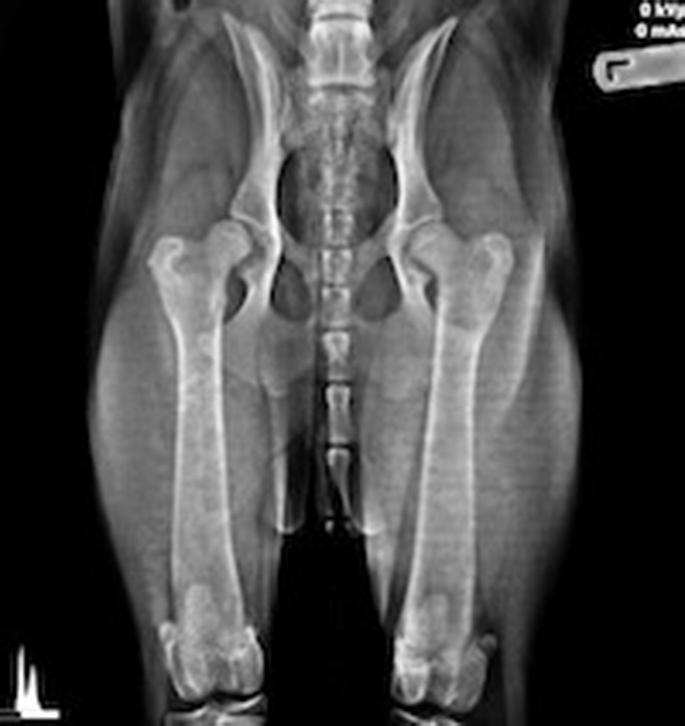

Radiographs were performed and showed severe hip laxity. Hip laxity is a term to define "loose ligaments" in which causes great pain and uncomfort to a patient and carries a high risk of development of Osteoarthritis.